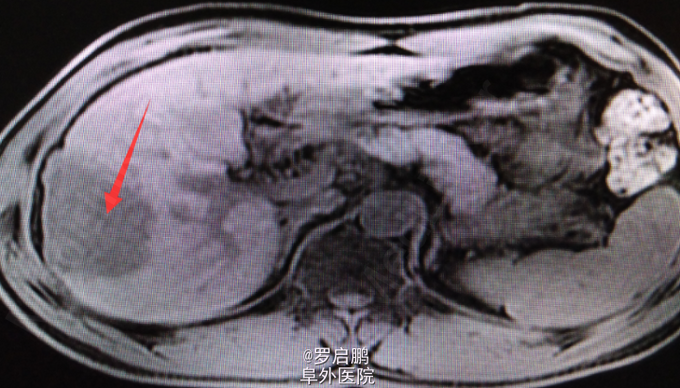

患者 男 48岁 主诉:发现肝脏占位半月 现病史:半月前患者因慢性乙型肝炎复查腹部超声发现右肝占位 既往:慢性乙肝20年,未规律治疗。 个人史:吸烟史25年20支/天,饮酒史13年,白酒2两/次。

超声:右肝高回声光团,胆囊、肝内外胆管、脾脏、双肾未见异常 腹部MRI:肝右叶占位 腹部平扫+增强:肝右叶占位,肝内多发小密度,左肾囊肿,腹膜后淋巴结肿大

肝右叶占位,肝癌? 前入路右半肝切除,LC 鉴别诊断:原发性肝癌;肝转移癌;肝海绵状血管瘤;肝腺瘤;血管平滑肌脂肪瘤。

注意术中循环维持,备血、血浆。术中平稳。术中病理:(右半肝)低分化胆管腺癌,可见坏死,肝内可见多发卫星灶,紧邻肝被膜,切缘未见特殊。术后恢复良好出院。